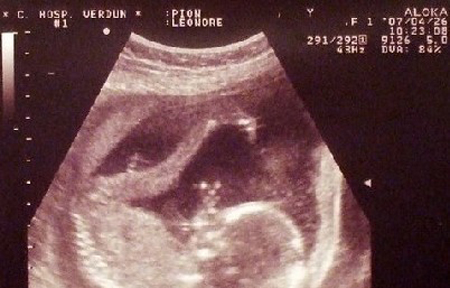

到现在已经怀宝宝4个月了,去做检查一切健康,老公一家人都很高兴。婆婆为了让我好好养胎,什么都不让我做,没几个月我就胖了一圈。想想这几年为了满足老公心愿添个男丁,受了多少罪,不过还好通过试管婴儿实现了愿望,非常感谢泰国的医生和护士们。